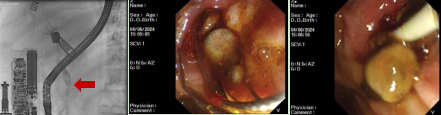

患者,女,77岁,主因“皮肤黄染、烧心、乏力1个月”入院,既往患高血压、糖尿病、冠心病10余年,曾因“病窦综合征”行起搏器植入术,有胆囊切除病史。腹部增强CT提示:壶腹周围占位继发胆道系统梗阻可能,腹膜后淋巴结转移可能。给予患者内镜下逆行胰胆管造影术并给予胆道金属支架置入。

患者,女,76岁,主因“间断上腹部饱胀不适伴疼痛1个月”就诊我科,既往胆囊切除史。腹部CT提示胆总管结石。因患者结石较大,行内镜下逆行胰胆管造影术并给予胆道支架置入治疗。术后患者病情平稳,恢复良好。择期行内镜下胆总管结石取石治疗。